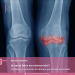

Descubra mais sobre Artrite Reumatóide